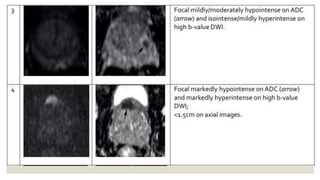

◦ Diffusion weighted imaging (DWI)

◦ 1: no abnormality and ADC and high b-value DWI

◦ 2: indistinct hypointense on ADC

◦ 3: focal mildly/moderately hypointense on ADC and isointense/mildly hyperintense on high b-value DWI

◦ 4: focal markedly hypointense on ADC hyperintense on high b-value DWI; <1.5 cm in greatest

dimension

◦ 5: same as 4 but ≥1.5 cm in greatest dimension or definite extraprostatic extension/invasive behavior